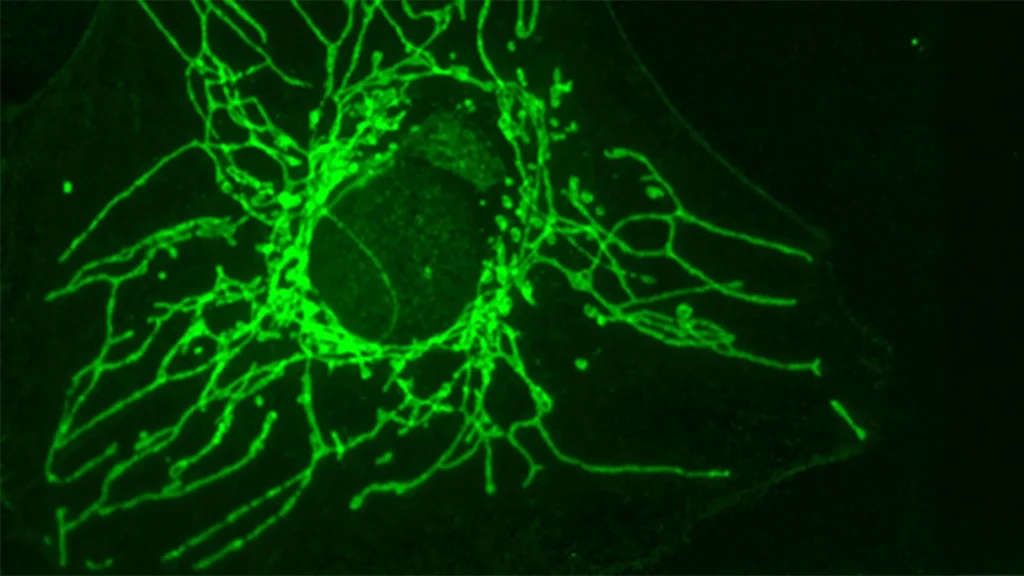

Os pesquisadores, liderados por Jean-Claude Martinou, Professor Emérito no Departamento de Biologia Molecular e Celular da Faculdade de Ciências da UNIGE, investigaram como vários aminoácidos influenciam o crescimento de células cancerosas. Seus experimentos revelaram que a versão D da cisteína (D-Cys), que contém um átomo de enxofre, pode inibir de maneira significativa o crescimento de certas células cancerosas em experimentos de laboratório. No entanto, células saudáveis não foram afetadas.

“Essa diferença entre células cancerosas e saudáveis é facilmente explicada: D-Cys é importada para as células através de um transportador específico que está presente apenas na superfície de certas células cancerosas,” explica Joséphine Zangari, estudante de doutorado no laboratório do Professor Martinou e primeira autora do estudo. “Na verdade, observamos que se expressarmos esse transportador na superfície de células saudáveis, essas células param de proliferar na presença de D-Cys.”